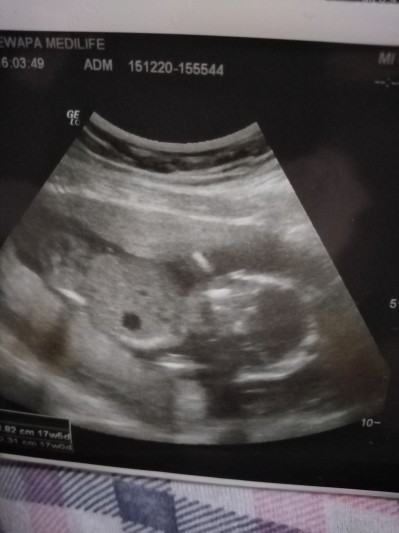

Kızlar 17+5 bugun cinsiyet İcin gittik ama tam birşey demedi sizce cinsiyeti ne anlayan varmı

Gebelik haftası 17+5

Yanlış foto paylaştım telrardan bakın canım doktor kıza benziyor ama net birşey diyemiyorum dedi degişe bilir dedi sizce degişirmi

Kesesi erkeğe benziyo canım

Kız bence canım